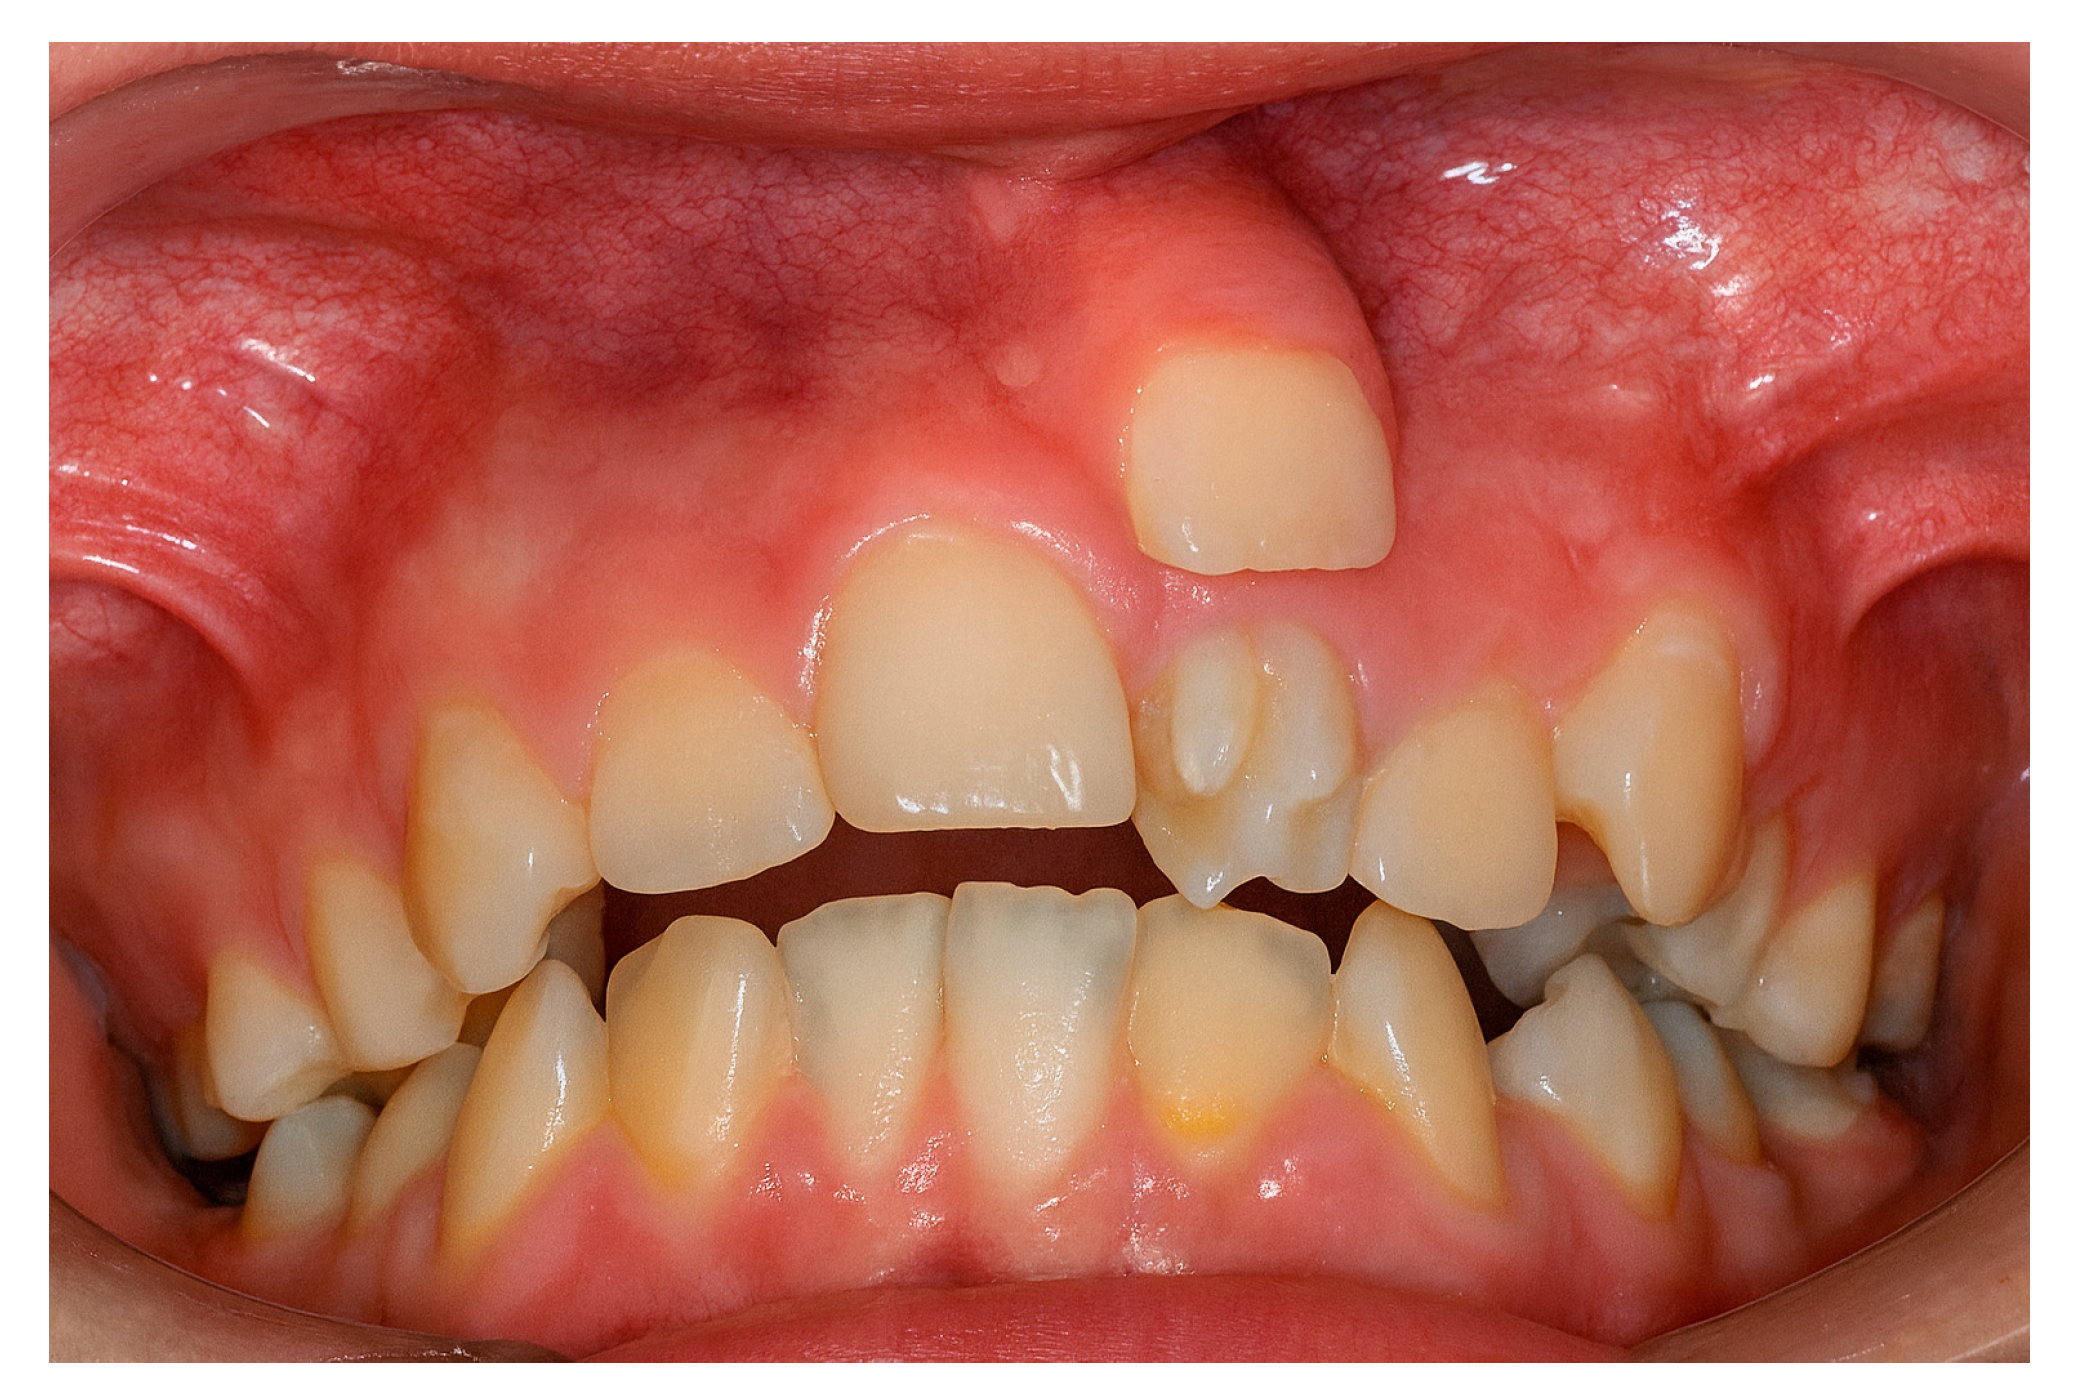

The increased frequency of ST in the maxillary incisor region (Figure 2) may be linked to intricate tissue rearrangements and morphogenetic activity in this area [2,17,20,25]. Nevertheless, no single theory fully accounts for the wide diversity of clinical presentations, suggesting that the etiology of ST is multifactorial, shaped by a complex interplay between genetic predisposition and environmental influences [3,24].

Figure 2. Supernumerary teeth located in the maxillary incisor area.